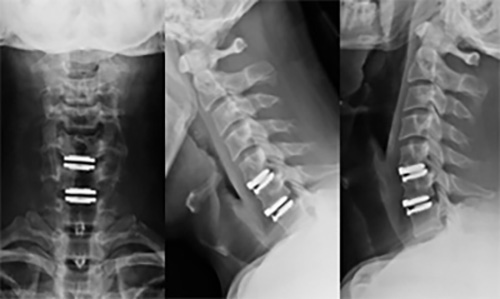

하지만 증상이 심하지 않은 경우, 보존적 치료를 통해 호전될 수 있습니다. 보존적 치료에는 휴식, 약물치료, 물리치료, 운동치료 등이 있습니다. 그러나 증상이 심한 경우에는 수술이 필요할 수 있습니다.